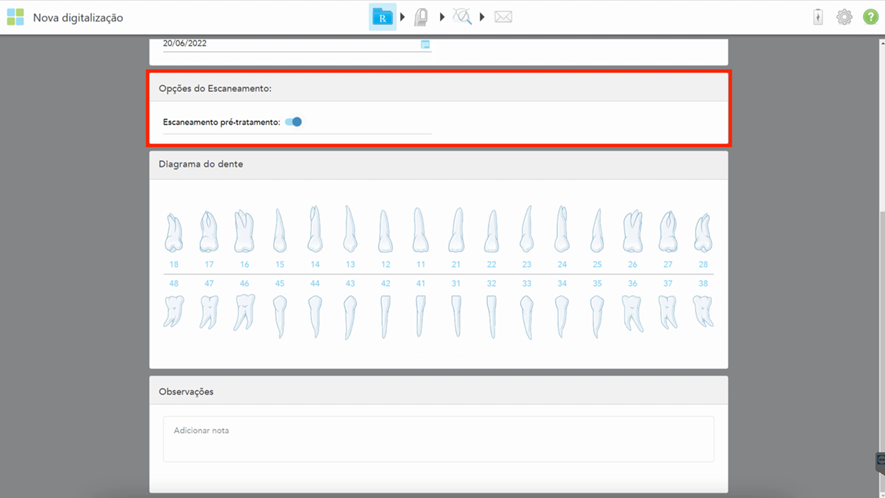

3- Com o scanner iTero, executamos escaneamento no modo restaurativo com a opção escaneamento pré-tratamento. Marque a caixa de seleção escaneamento pré-tratamento (Figura 2)toda vez que desejar digitalizar o paciente que possui uma prótese provisória e que esteja excelente, tanto esteticamente quanto funcionalmente. O escaneamento pré-tratamento permite que o laboratório de prótese dentária copie a anatomia original da prótese provisória para a prótese definitiva. Em outros scanners teremos que realizar três escaneamentos separados (1. escaneamento da prótese provisória aparafusada na boca; 2. escaneamento dos transferentes digitais; 3. escaneamento do antagonista com registro oclusal).